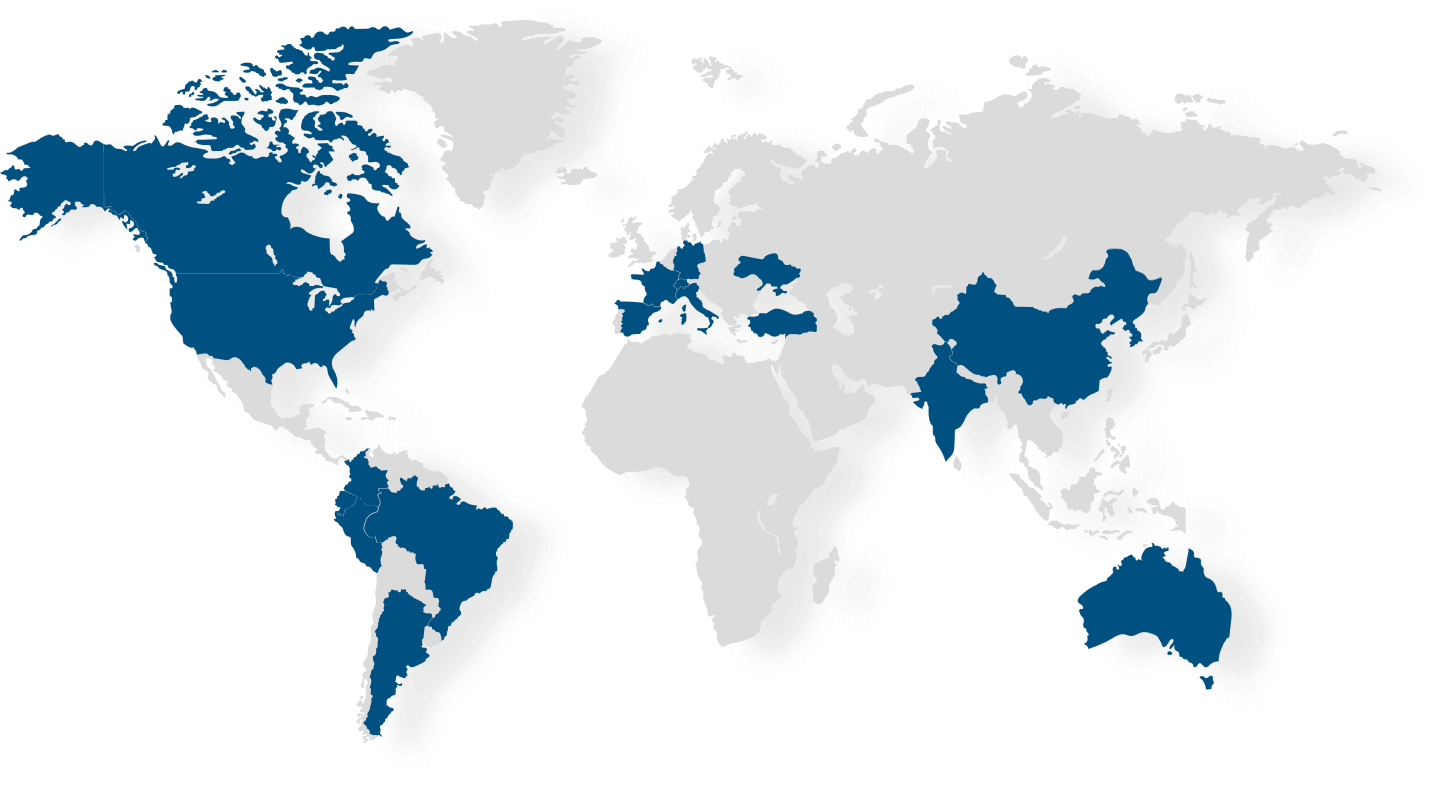

Health supPly en el mundo

Health Supply ofrece a pacientes y profesionales de la salud, medicamentos difíciles de

encontrar en sus países, por escasez o falta de registro sanitario, siempre anteponemos la

seguridad del paciente y cumplimos con las normativas legales. Para lograr este objetivo,

contamos con una amplia red de distribuidores y laboratorios asociados en 4 continentes y más

de 18 países. Nuestra fortaleza es ofrecer todo tipo de medicamentos, alineándonos a las

necesidades específicas de cada paciente.

Quienes somos

Con más de 20 años de experiencia en el mercado farmacéutico y especialmente en el área Oncológica, se evidenció que, en países emergentes, no se podían realizar el 100% de los tratamientos indicados a pacientes por falta de acceso a medicamentos. En el 2007 HSP es fundada, con el objetivo de ofrecer productos no disponibles en países emergentes apacientes de enfermedades graves.